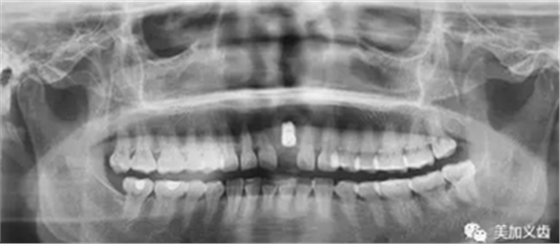

3.牙科CT掃描,種植計(jì)劃

頜面部CBCT掃描,頜骨三維建模。在CBCT數(shù)據(jù)處理軟件中標(biāo)記出重要的神經(jīng)、血管、上頜竇等關(guān)鍵解剖標(biāo)志。將上述CAD/CAM軟件中完成的冠橋CAD數(shù)據(jù)導(dǎo)入CBCT軟件,.STL格式的牙頜模型與DICOM格式的CT牙頜骨模型配準(zhǔn)整合,選擇合適的植體,避開重要解剖結(jié)構(gòu),設(shè)計(jì)安全的種植體植入位置與角度,實(shí)現(xiàn)以生理性修復(fù)為導(dǎo)向的種植規(guī)劃。